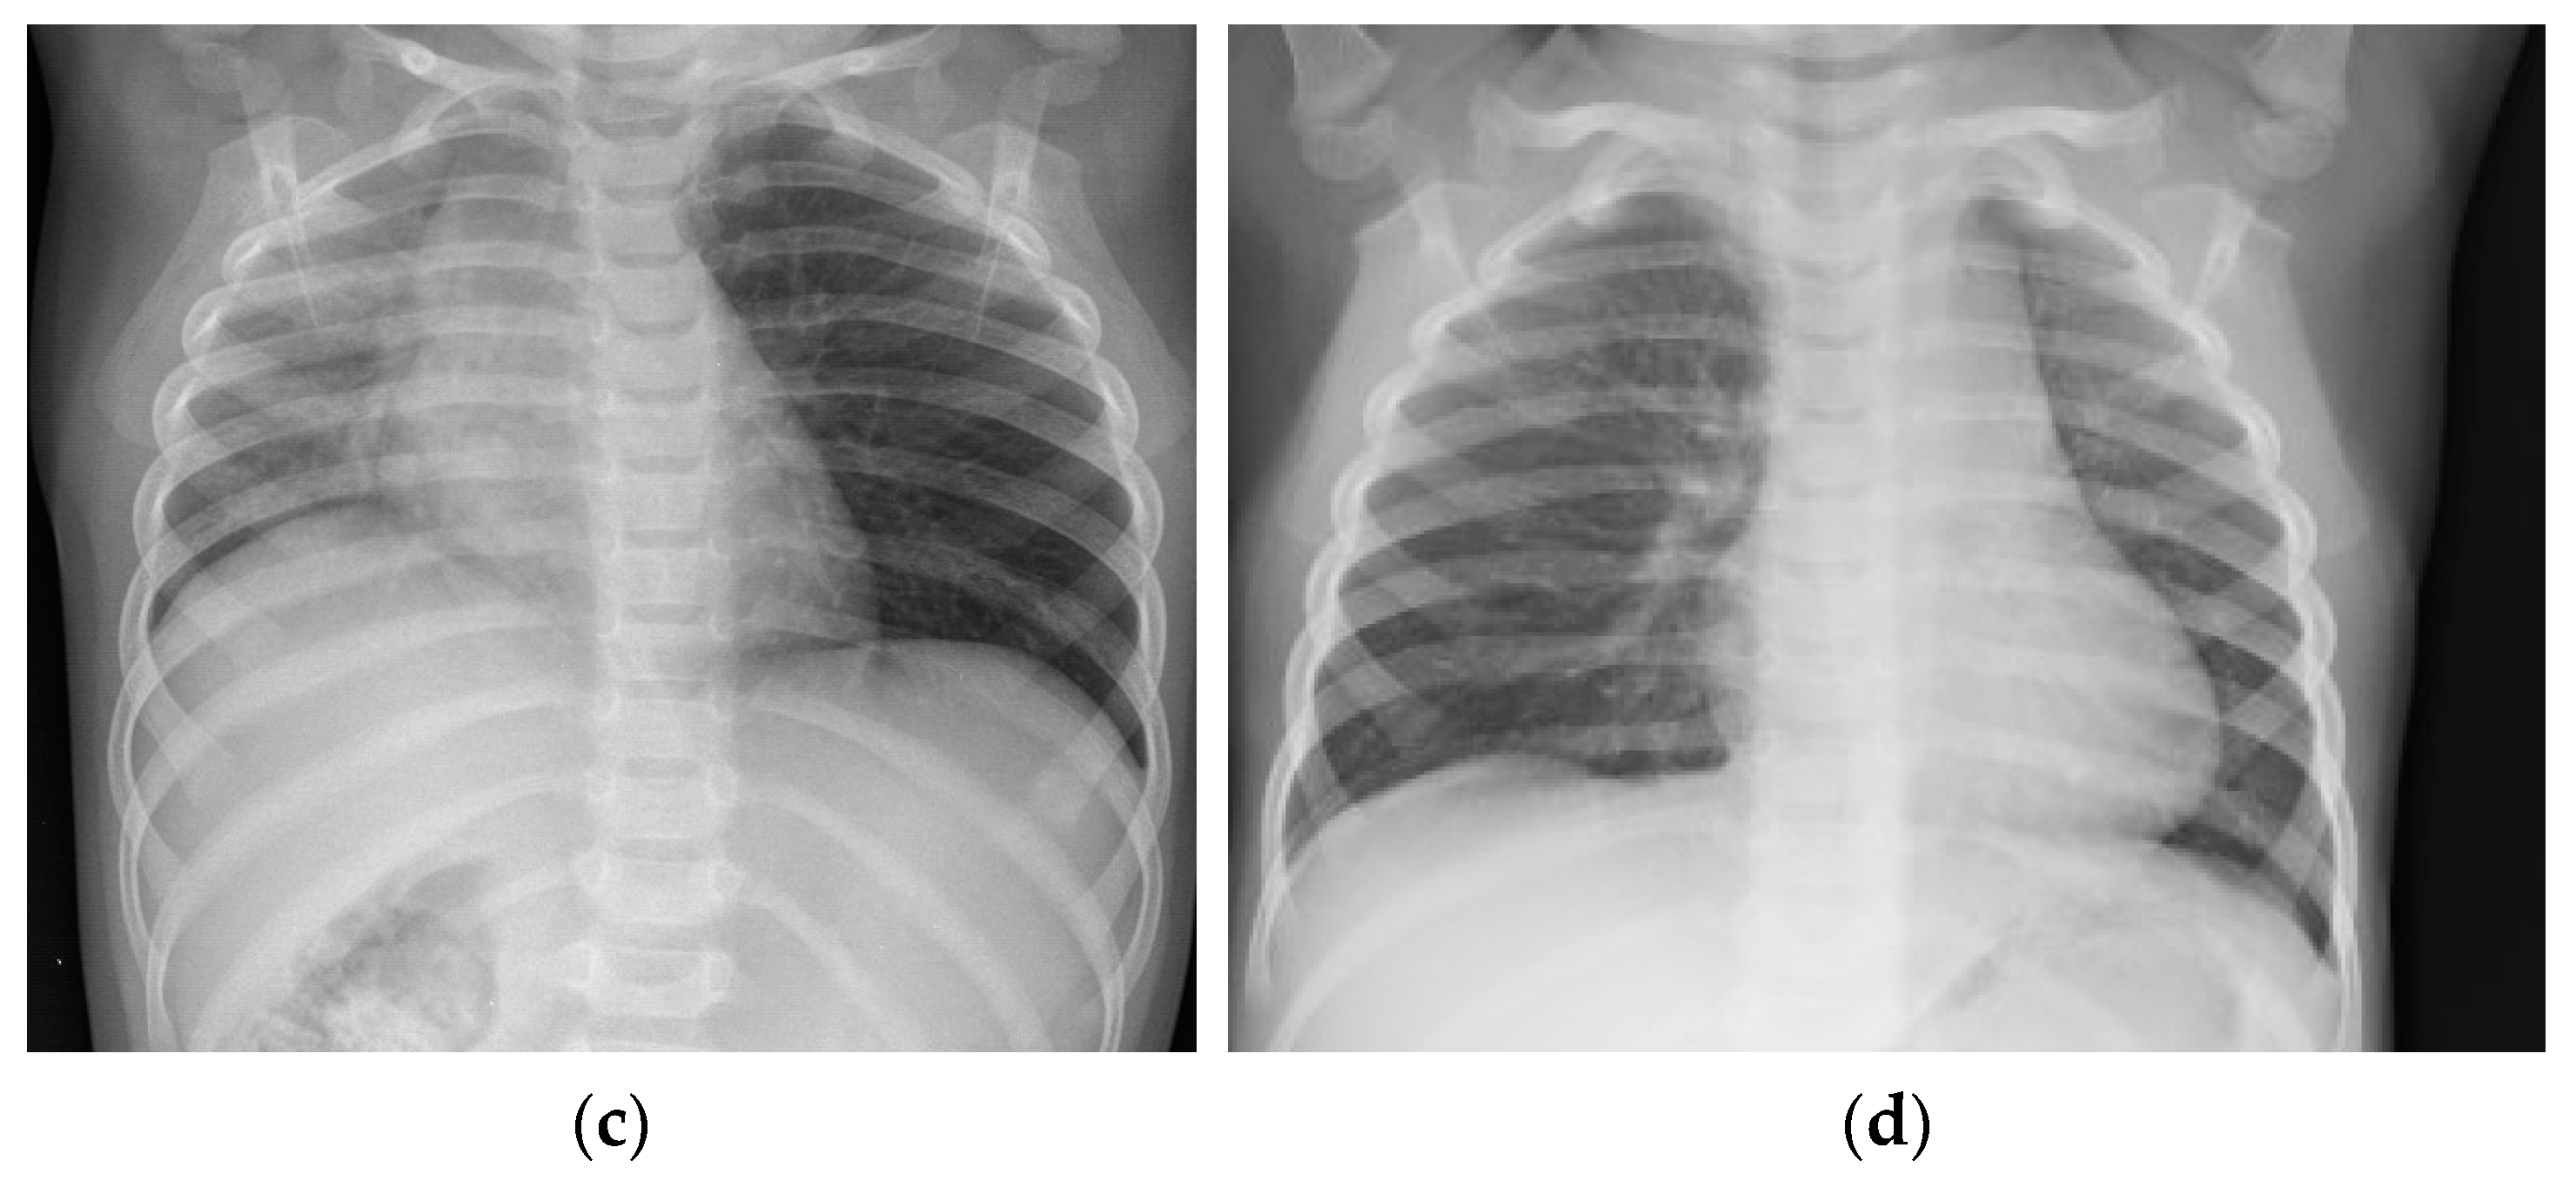

In the analyzed group, X-ray imaging results included: evidence of foreign body (metal objects), unilateral pneumothorax or atelectasis, intensified vascular pattern, emphysema, and mediastinum dislocation (Figure 3).

Figure 3.

X-ray imaging results. (a) Evidence of foreign body in right bronchi; (b) intensified vascular pattern; (c) mediastinum dislocation to right side; (d) mediastinum dislocation to left side.

When physical examination reveals dyspnea, cough, and excessive respiratory effort or fever, and chest X-ray image presumes a plausible foreign body aspiration, even if no choking episode was observed, it is recommended that rigid bronchoscopy be performed. Oversight and foreign body retention in lower airways may lead to serious adverse results [,]. Chest X-ray may show obvious evidence of foreign body (metal objects), but most times, radiologic image indirectly suggests the presence of an obstacle in the lower airways; in these cases, unilateral pneumothorax or atelectasis, emphysema, and mediastinum dislocation could be observed [,].

Bilateral radiological changes have lesser diagnostic value compared to unilateral ones, but this does not exclude the possibility of foreign body aspiration. In one of the analyzed cases, a 14-year-old girl with cerebral palsy experienced a choking episode during an investigation of the passage of barium sulphate contrast medium through the gastrointestinal tract, which resulted in barium aspiration to the airways and required two bronchoscopies in a two-day interval in order to remove the remaining contrast medium.